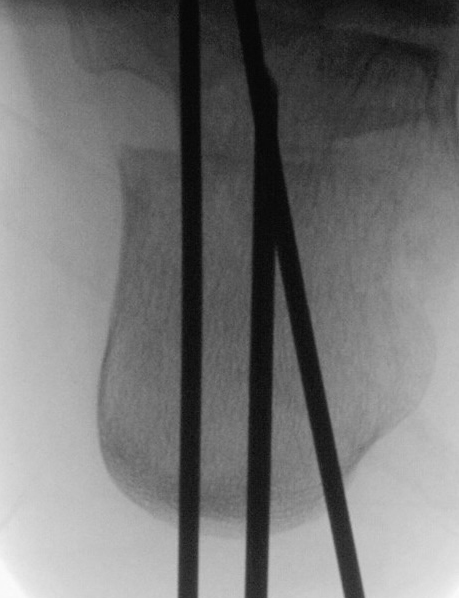

Zusätzlich schränken Wachstumsfugen die Wahl der Osteosynthese ein. Eine die Fuge kreuzende Osteosynthese ist ausschließlich mit Kirschner-Drähten möglich (Abb. 3).

Abb. 3 a-j: Beispiel einer Calcaneusverschiebeosteotomie mit offenen Wachstumsfugen und der entsprechenden Osteosynthese mit Kirschner Drähten. Lokalisation der Osteotomie (a), Lage der Fräse (b-d), Drahtlage mehrere Ansichten (e-h), Heilung der Osteotomie 4 Wochen postoperativ und Entfernung der Drähte (i-j).

Zum Lesen der Bildbeschreibung und zur Vollansicht bitte die Bilder anklicken. Bilder: A. Helmers.